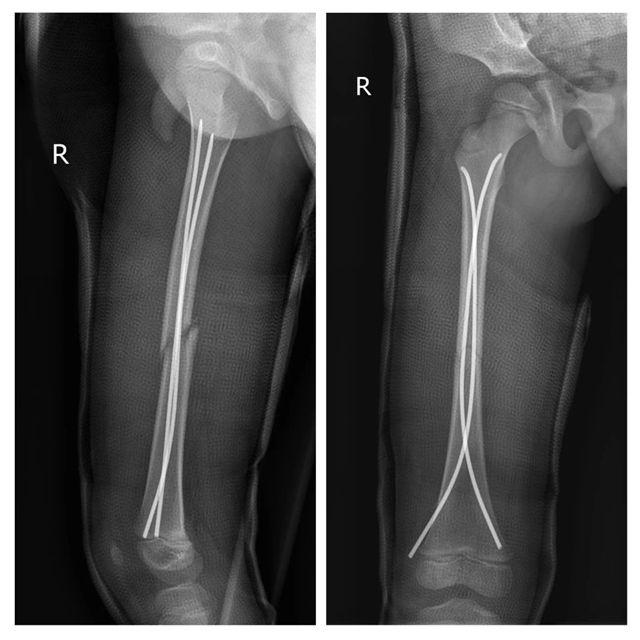

术前

术后

一切准备就绪后,陈孝均副教授、贺智榆主治医师先后为两位小朋友实施了股骨骨折闭合复位+弹性髓内钉固定术+髋人字石膏固定术。术后经过医护人员的悉心照料,两位小朋友顺利康复出院。

股骨骨折是儿童骨科比较常见的疾病,科室采用闭合复位弹性髓内钉治疗的方法治疗,该手术仅需在大腿两侧开2个微创伤口,具有创伤小、失血少、恢复快等优点。